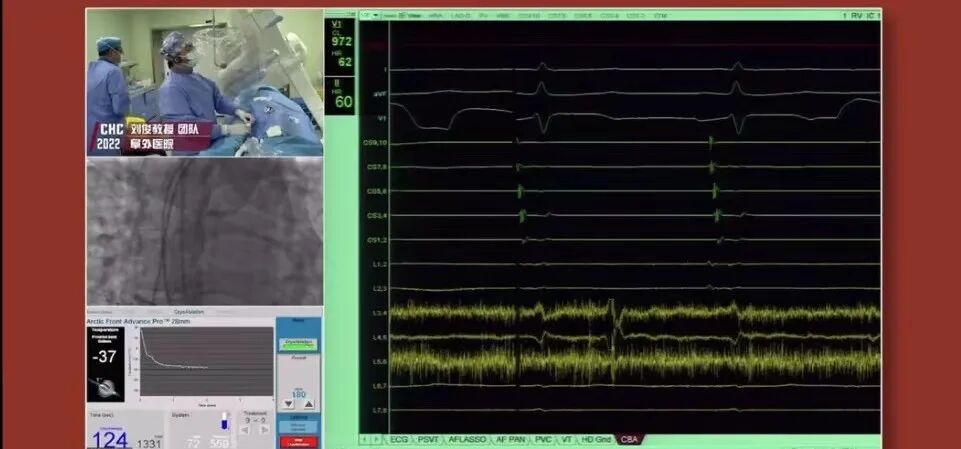

阜外心律失常中心:一病区 丁立刚教授团队、二病区 刘俊教授团队、三病区 唐闽教授团队